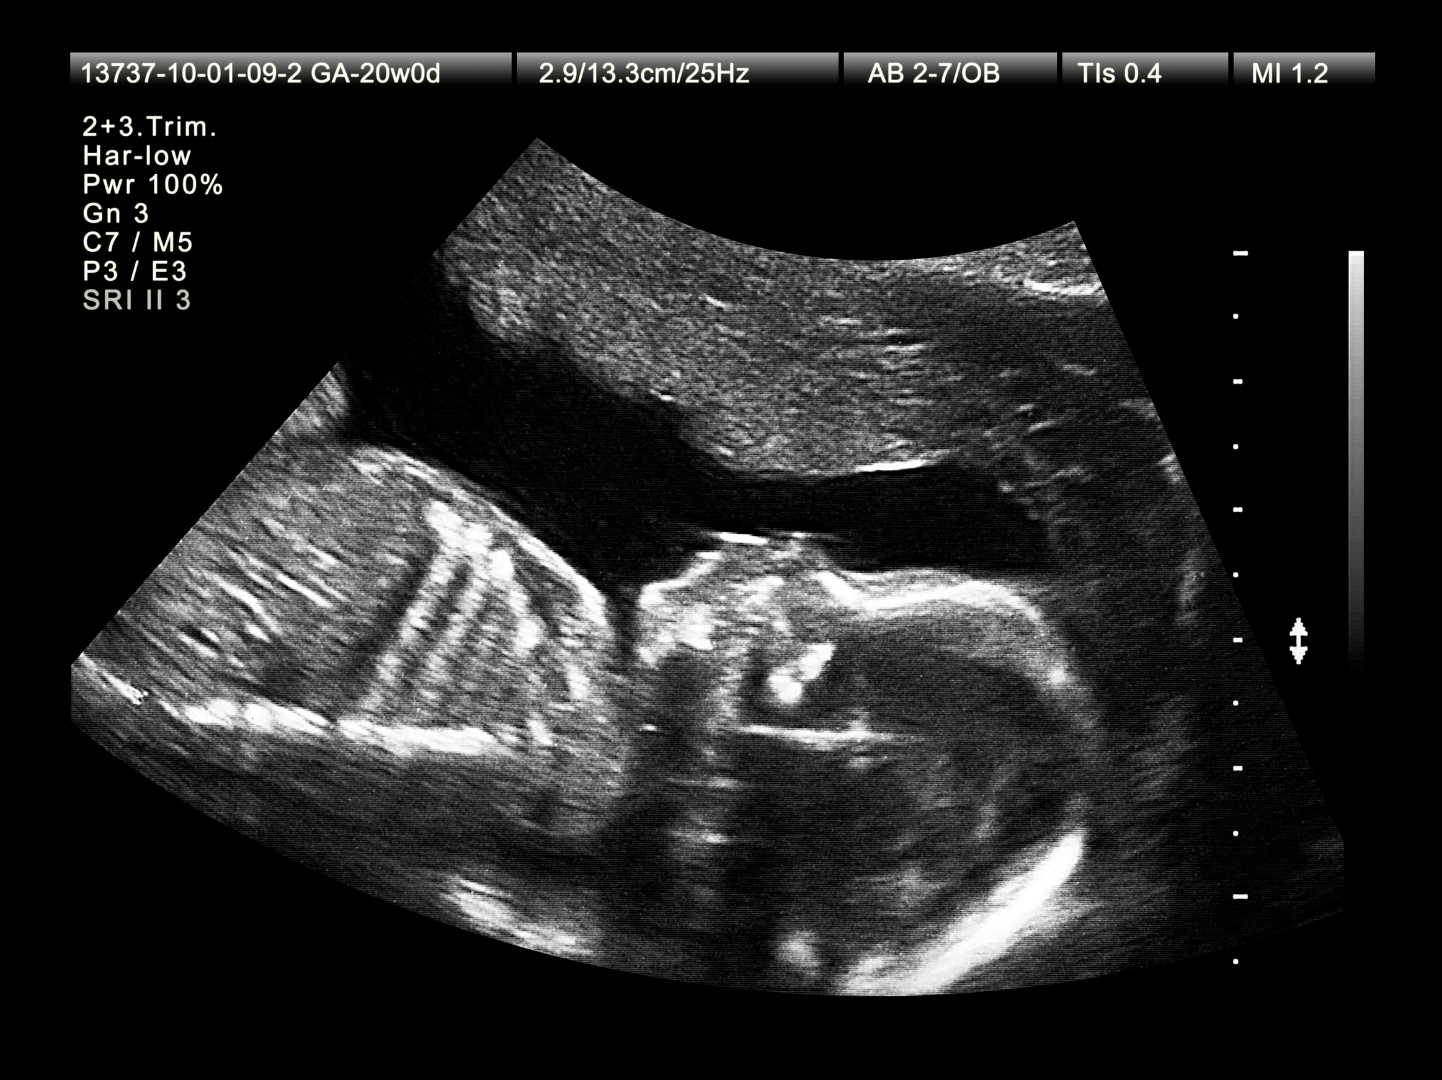

L’article, intitulé « Il est temps de changer la définition et le cadre réglementaire de la mortinatalité au Canada » (Time to change Canada’s stillbirth definition and regulatory framework), explique comment le taux de mortinatalité au Canada est « artificiellement élevé » par rapport à d’autres pays parce qu’il inclut les avortements pratiqués à partir de 20 semaines dans le décompte.

Les critères incluent l’exigence d’« enregistrer tous les décès fœtaux avec un poids de naissance de 500 g ou plus ou un âge gestationnel de 20 semaines ou plus », ajoute l’article. « Cependant, l’inclusion dans le nombre de mortinaissances des décès fœtaux qui suivent une interruption tardive de la grossesse (à 20 à 24 semaines de gestation) est un facteur clé du statut d’exception du Canada à l’échelle internationale. »